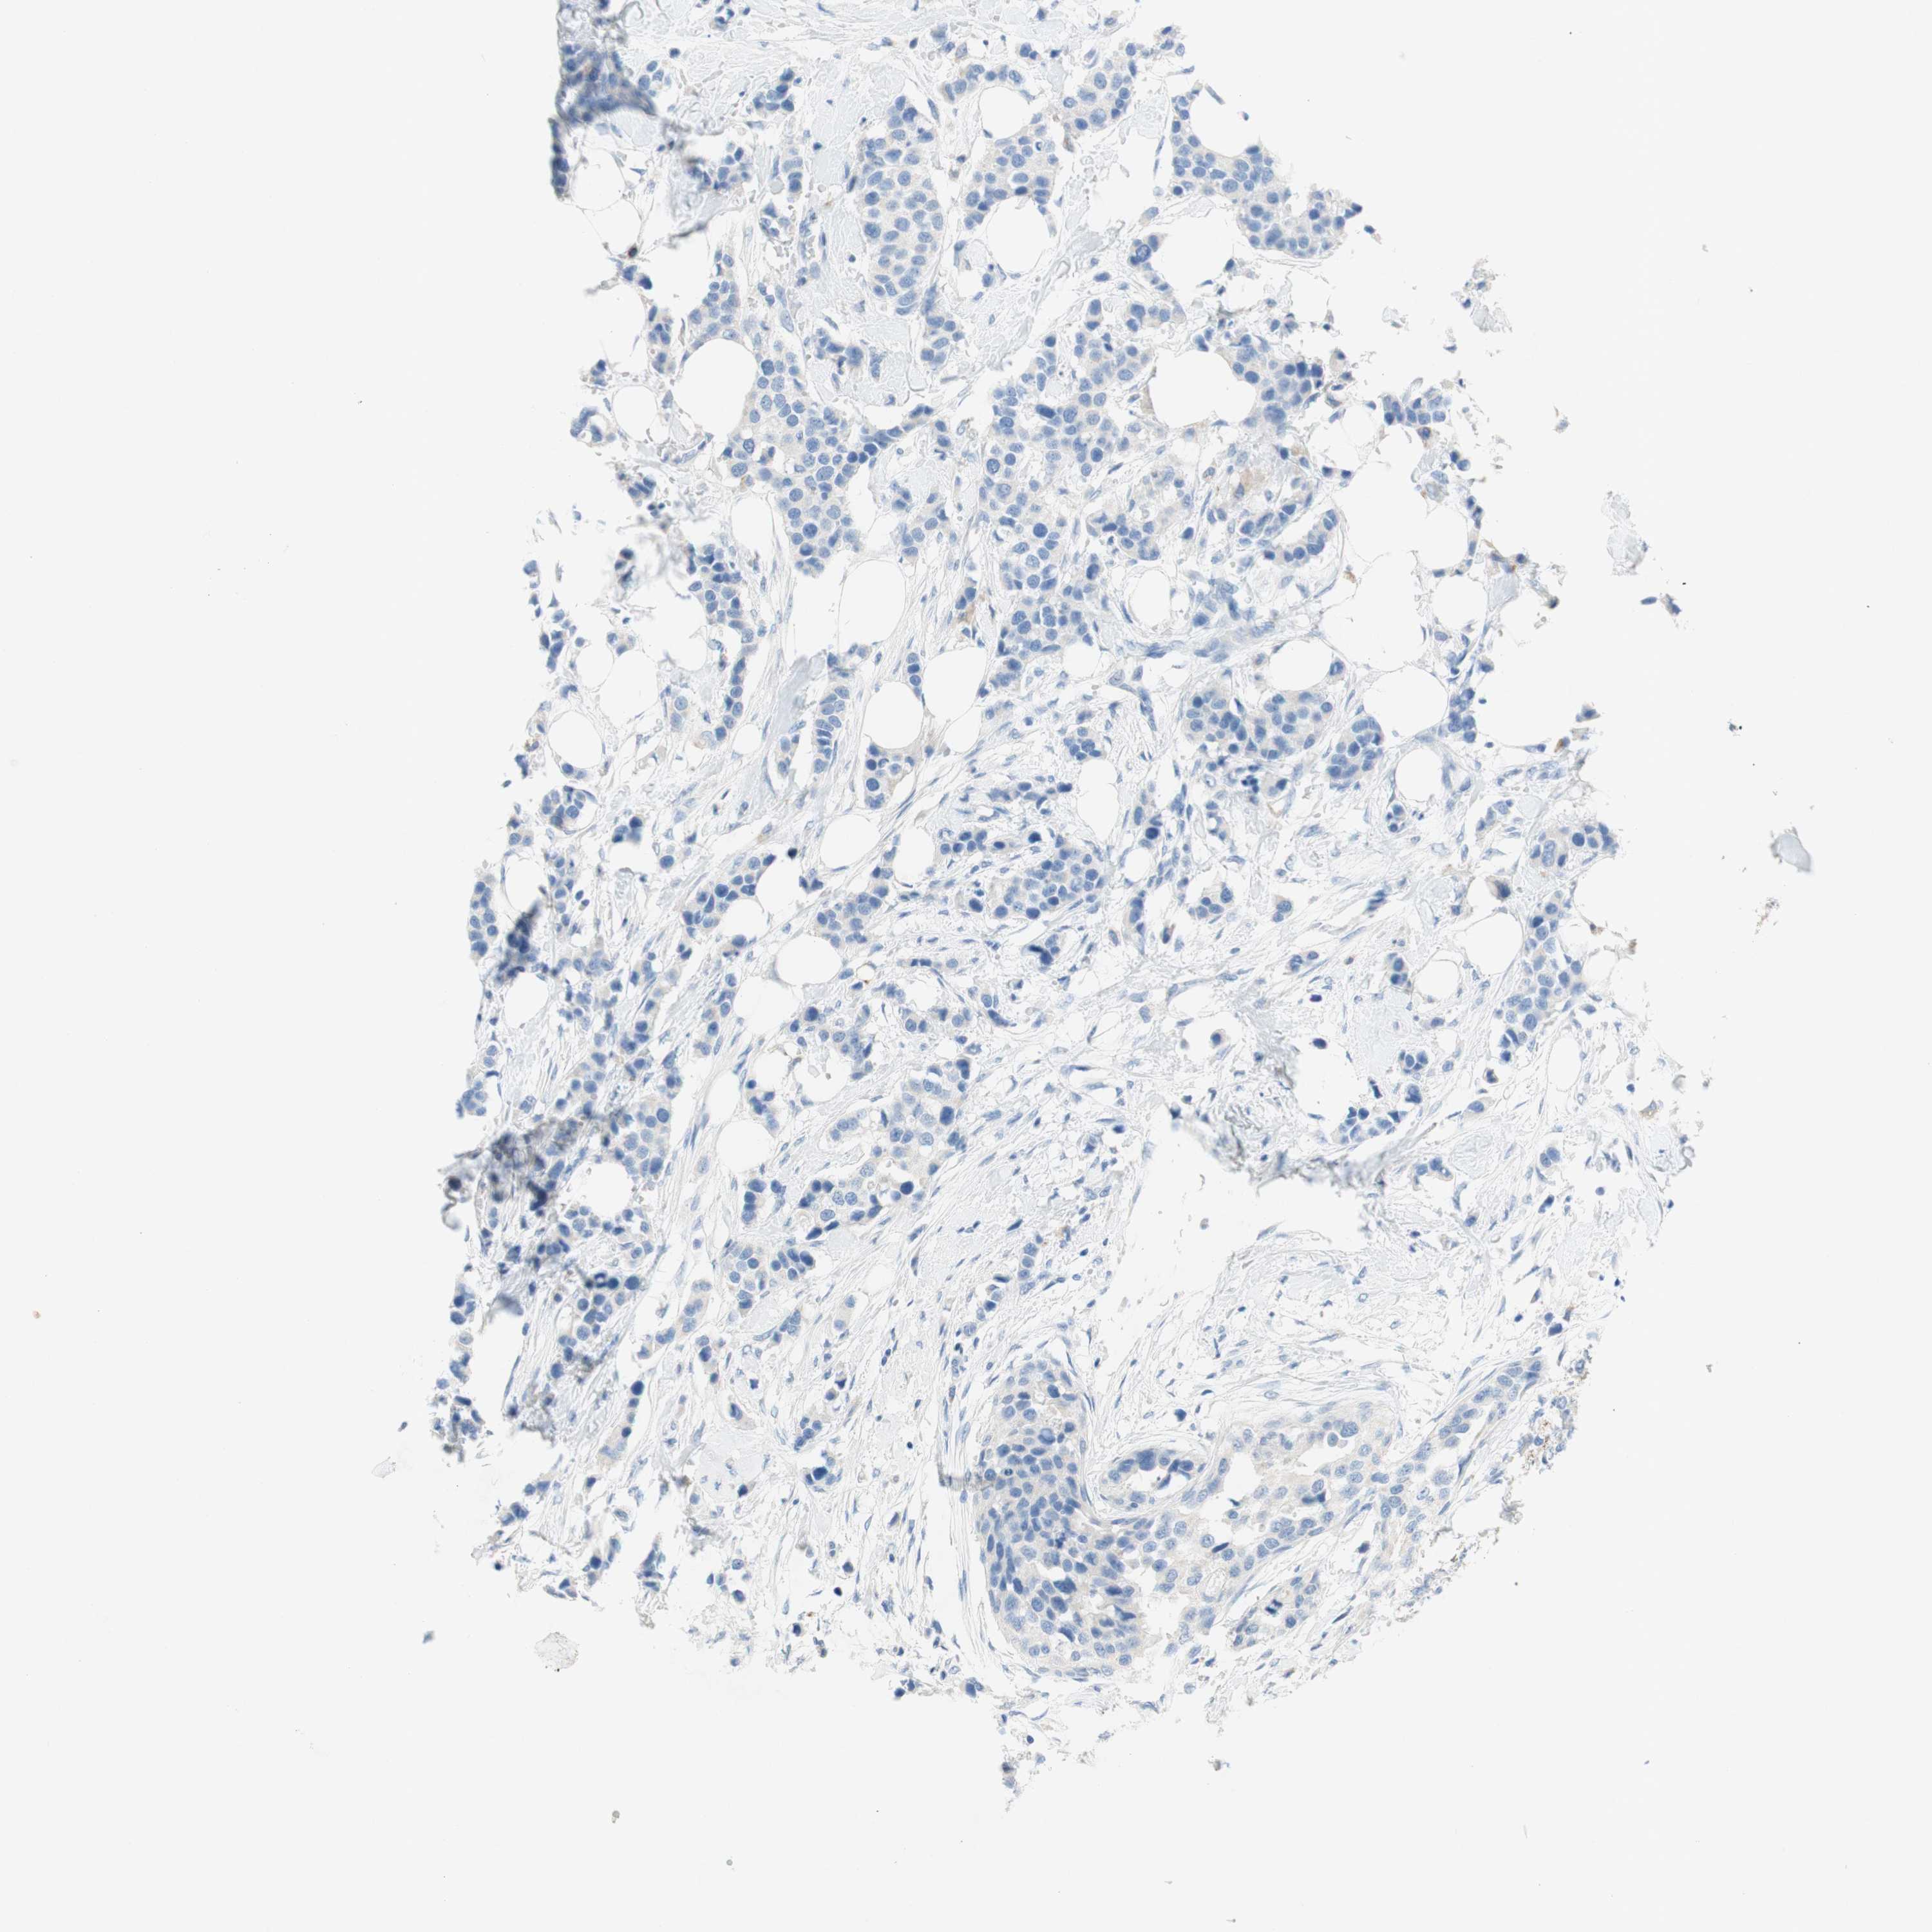

CANCER BREAST CANCER Show tissue menu

BRCA TCGA BRCA VALIDATION PROTEIN EXPRESSION